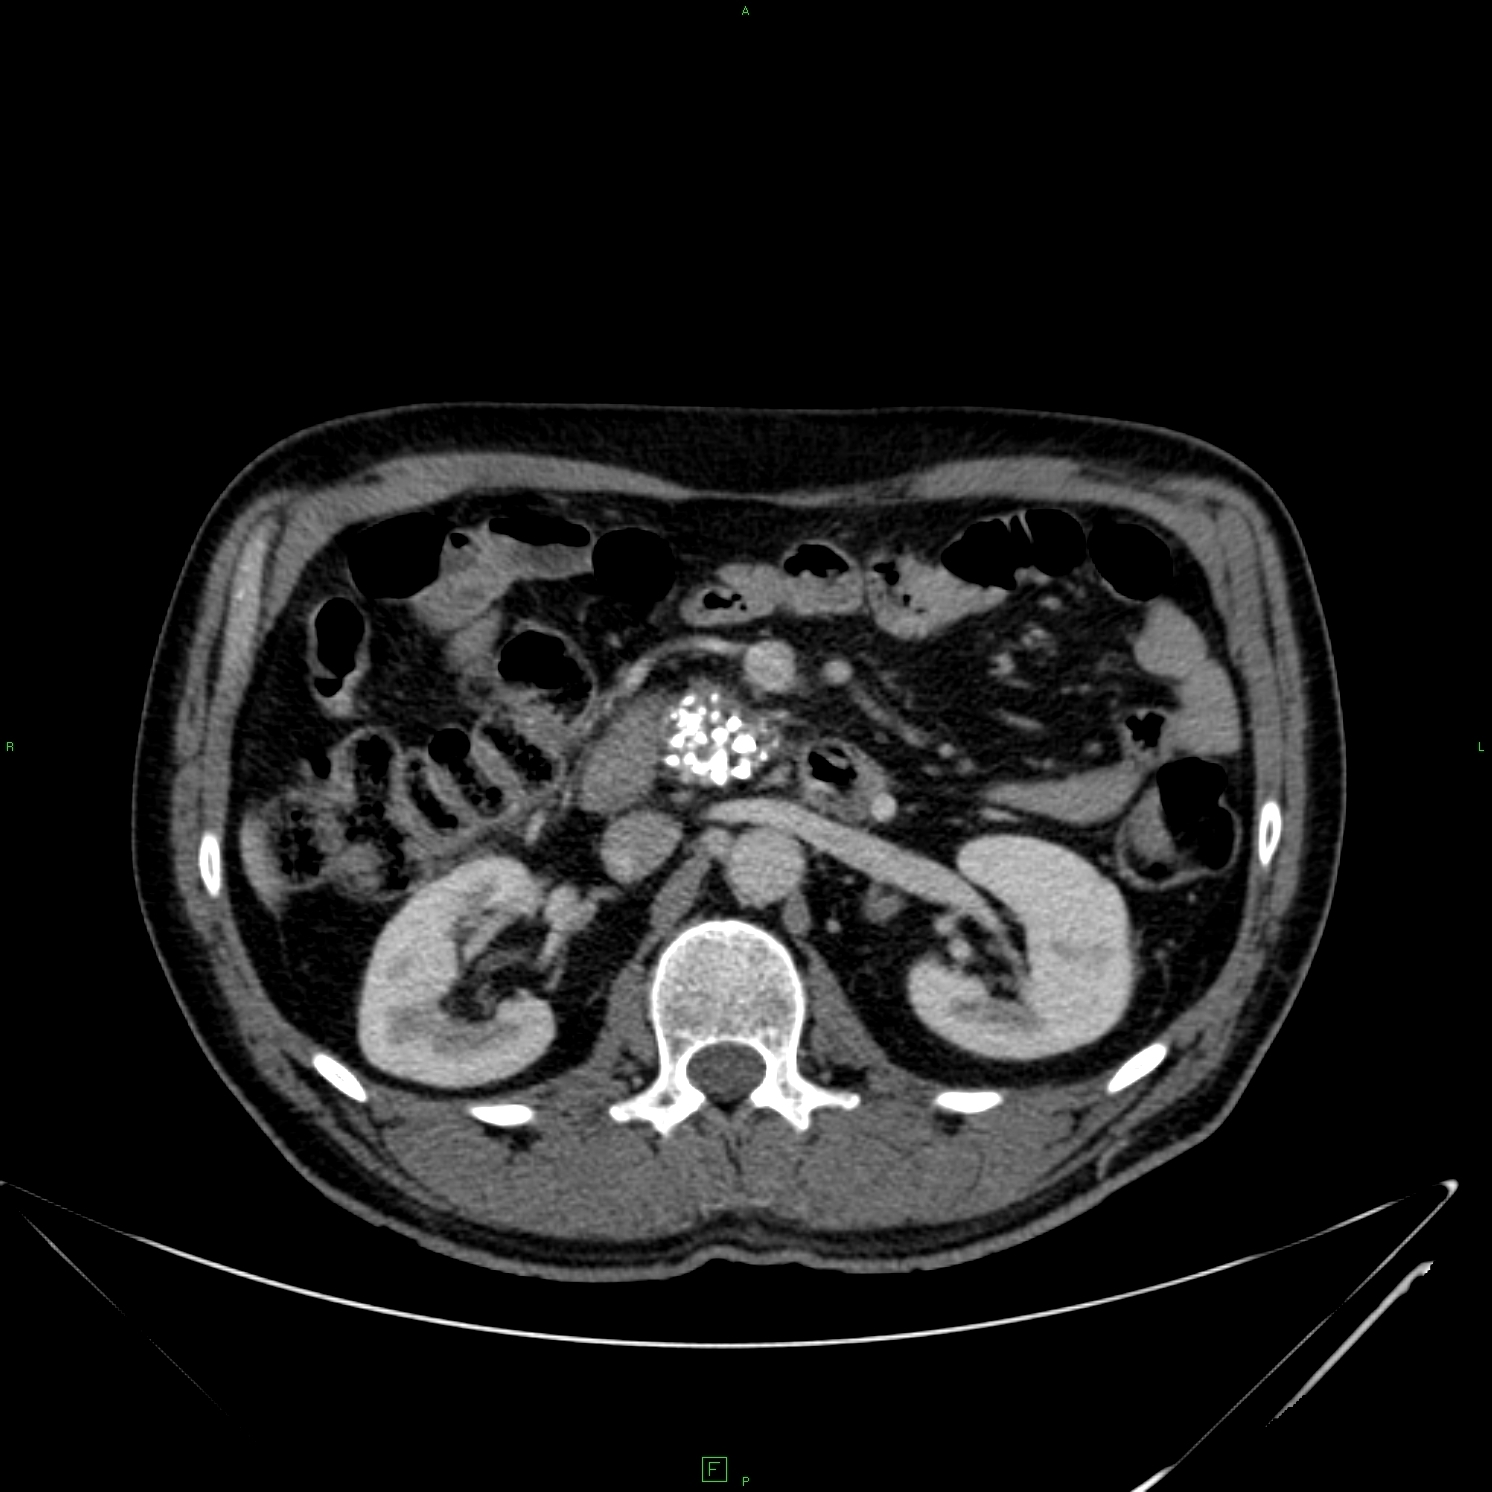

14.4.2.2. Chronic calcific pancreatitis:

Following the course and recovery of an acute pancreatitis minor-maior atrophy can be observed in the gland structure with calcifications of various extent, moreover quite rough calcifications can be seen sometimes along the pancreas gland structure. (Figure 43)

Figure 43: Chronic pancreatitis, rough calcifications on the head, contrast enhanced CT

Because of the calcification-related inhomogeneous structure and compression on the one hand Wirsung dilation, on the other hand tumor-suspicious areas can be observed. In case of clinical tumor suspicion and increased tumor marker PET-CT imaging can be necessary for the exact determination.